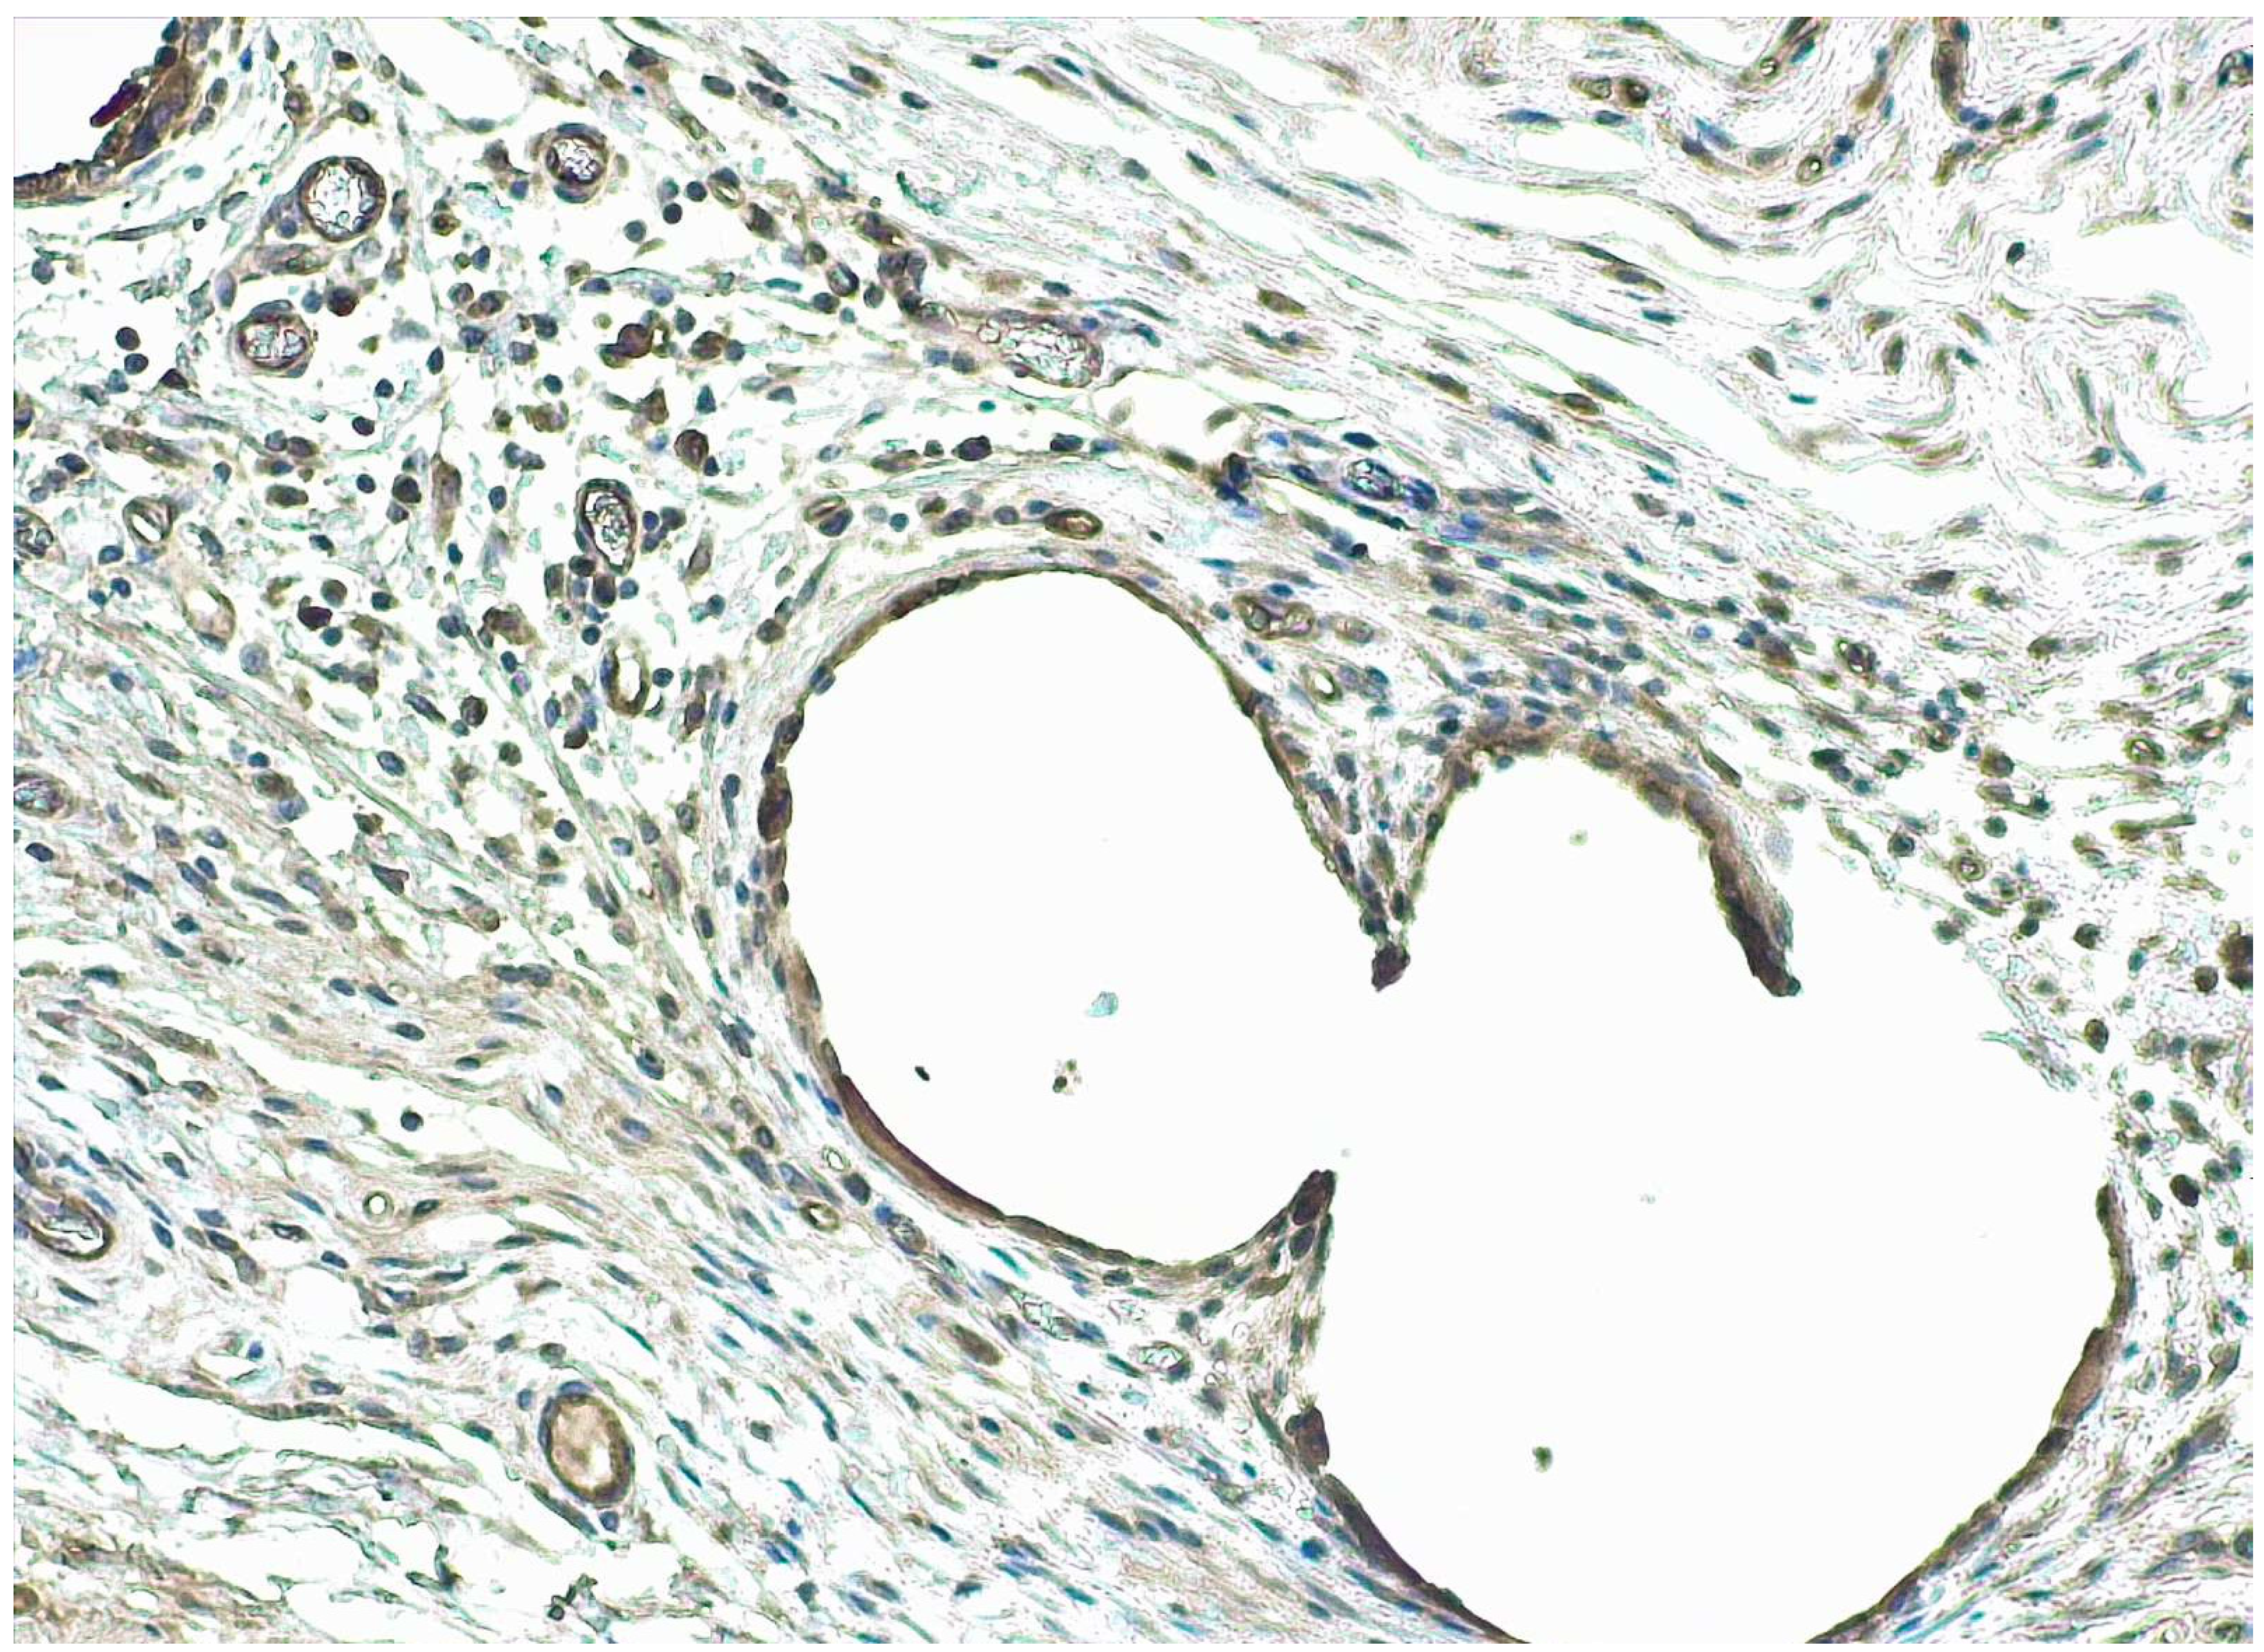

2.3. Histological Evaluation and Immunohistochemical Analysis

5.9. Statistical Analysis